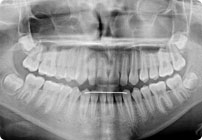

Antes

Caso: 11 años

Adolescente: Clase II

Mordida Cruzada Posterior

Sin extracción

Sin uso de expansores

6 alambres superiores

5 alambres inferiores

Sin uso de elásticos

Retenedores: Interior Fijo de TMA y Hawley en superior

Tiempo de tratamiento: 14 Visitas